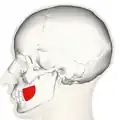

Bucinator outlined in red. | |

Position of buccinator muscle (red)

Position of buccinator muscle (red) -

Position of buccinator muscle (red)

Position of buccinator muscle (red) -

Position of buccinator muscle (red)

Position of buccinator muscle (red) -